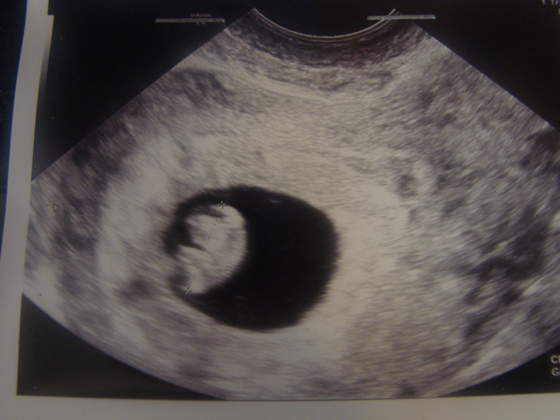

dziękuję mój suwaczek idealnie pasuje z wiekiem fasolinki. W środę było 7 tygodni i 1 dzień

Czyli Anisen jest szansa, że też zobaczę takie cudności Bo moje usg będzie równo w 8tyg.